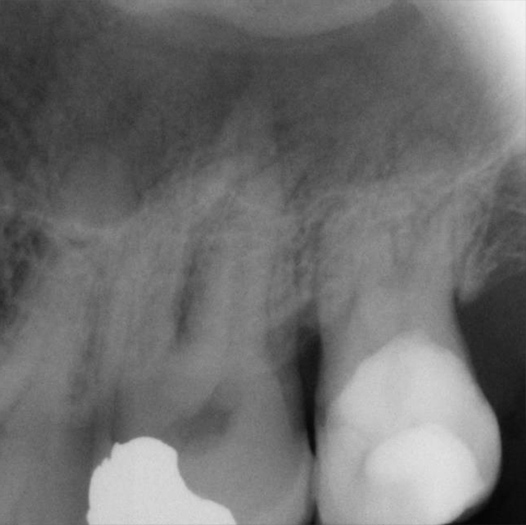

After

After Root Canal treatment